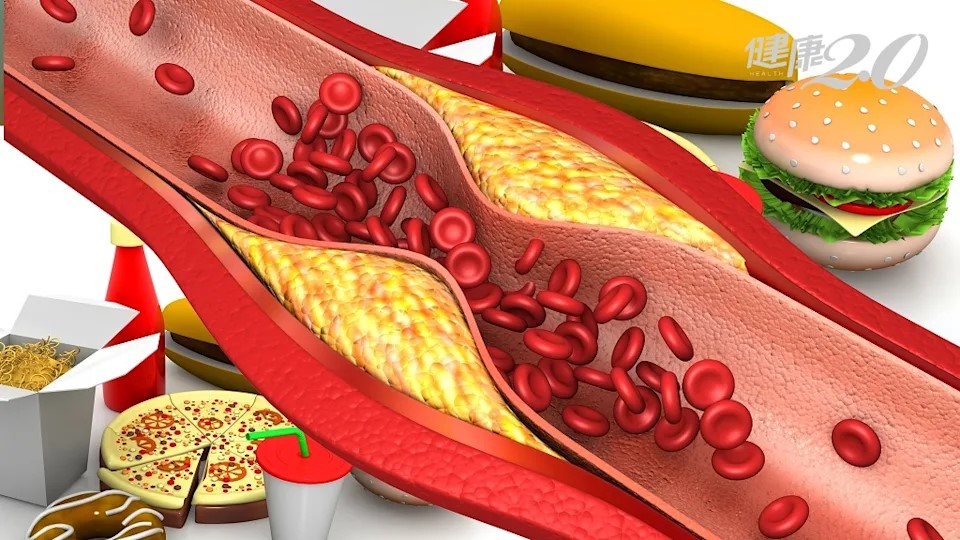

细胞~揭开富贵病背后的硬化真相

高盐、高脂、久坐、熬夜……现代生活方式在悄悄改变我们的身体。越来越多的人年纪轻轻就背上了“富贵病”标签——高血压、动脉粥样硬化、代谢综合症,这些表面看似无害的慢性病,其实正在深层次地侵蚀我们的心血管系统。